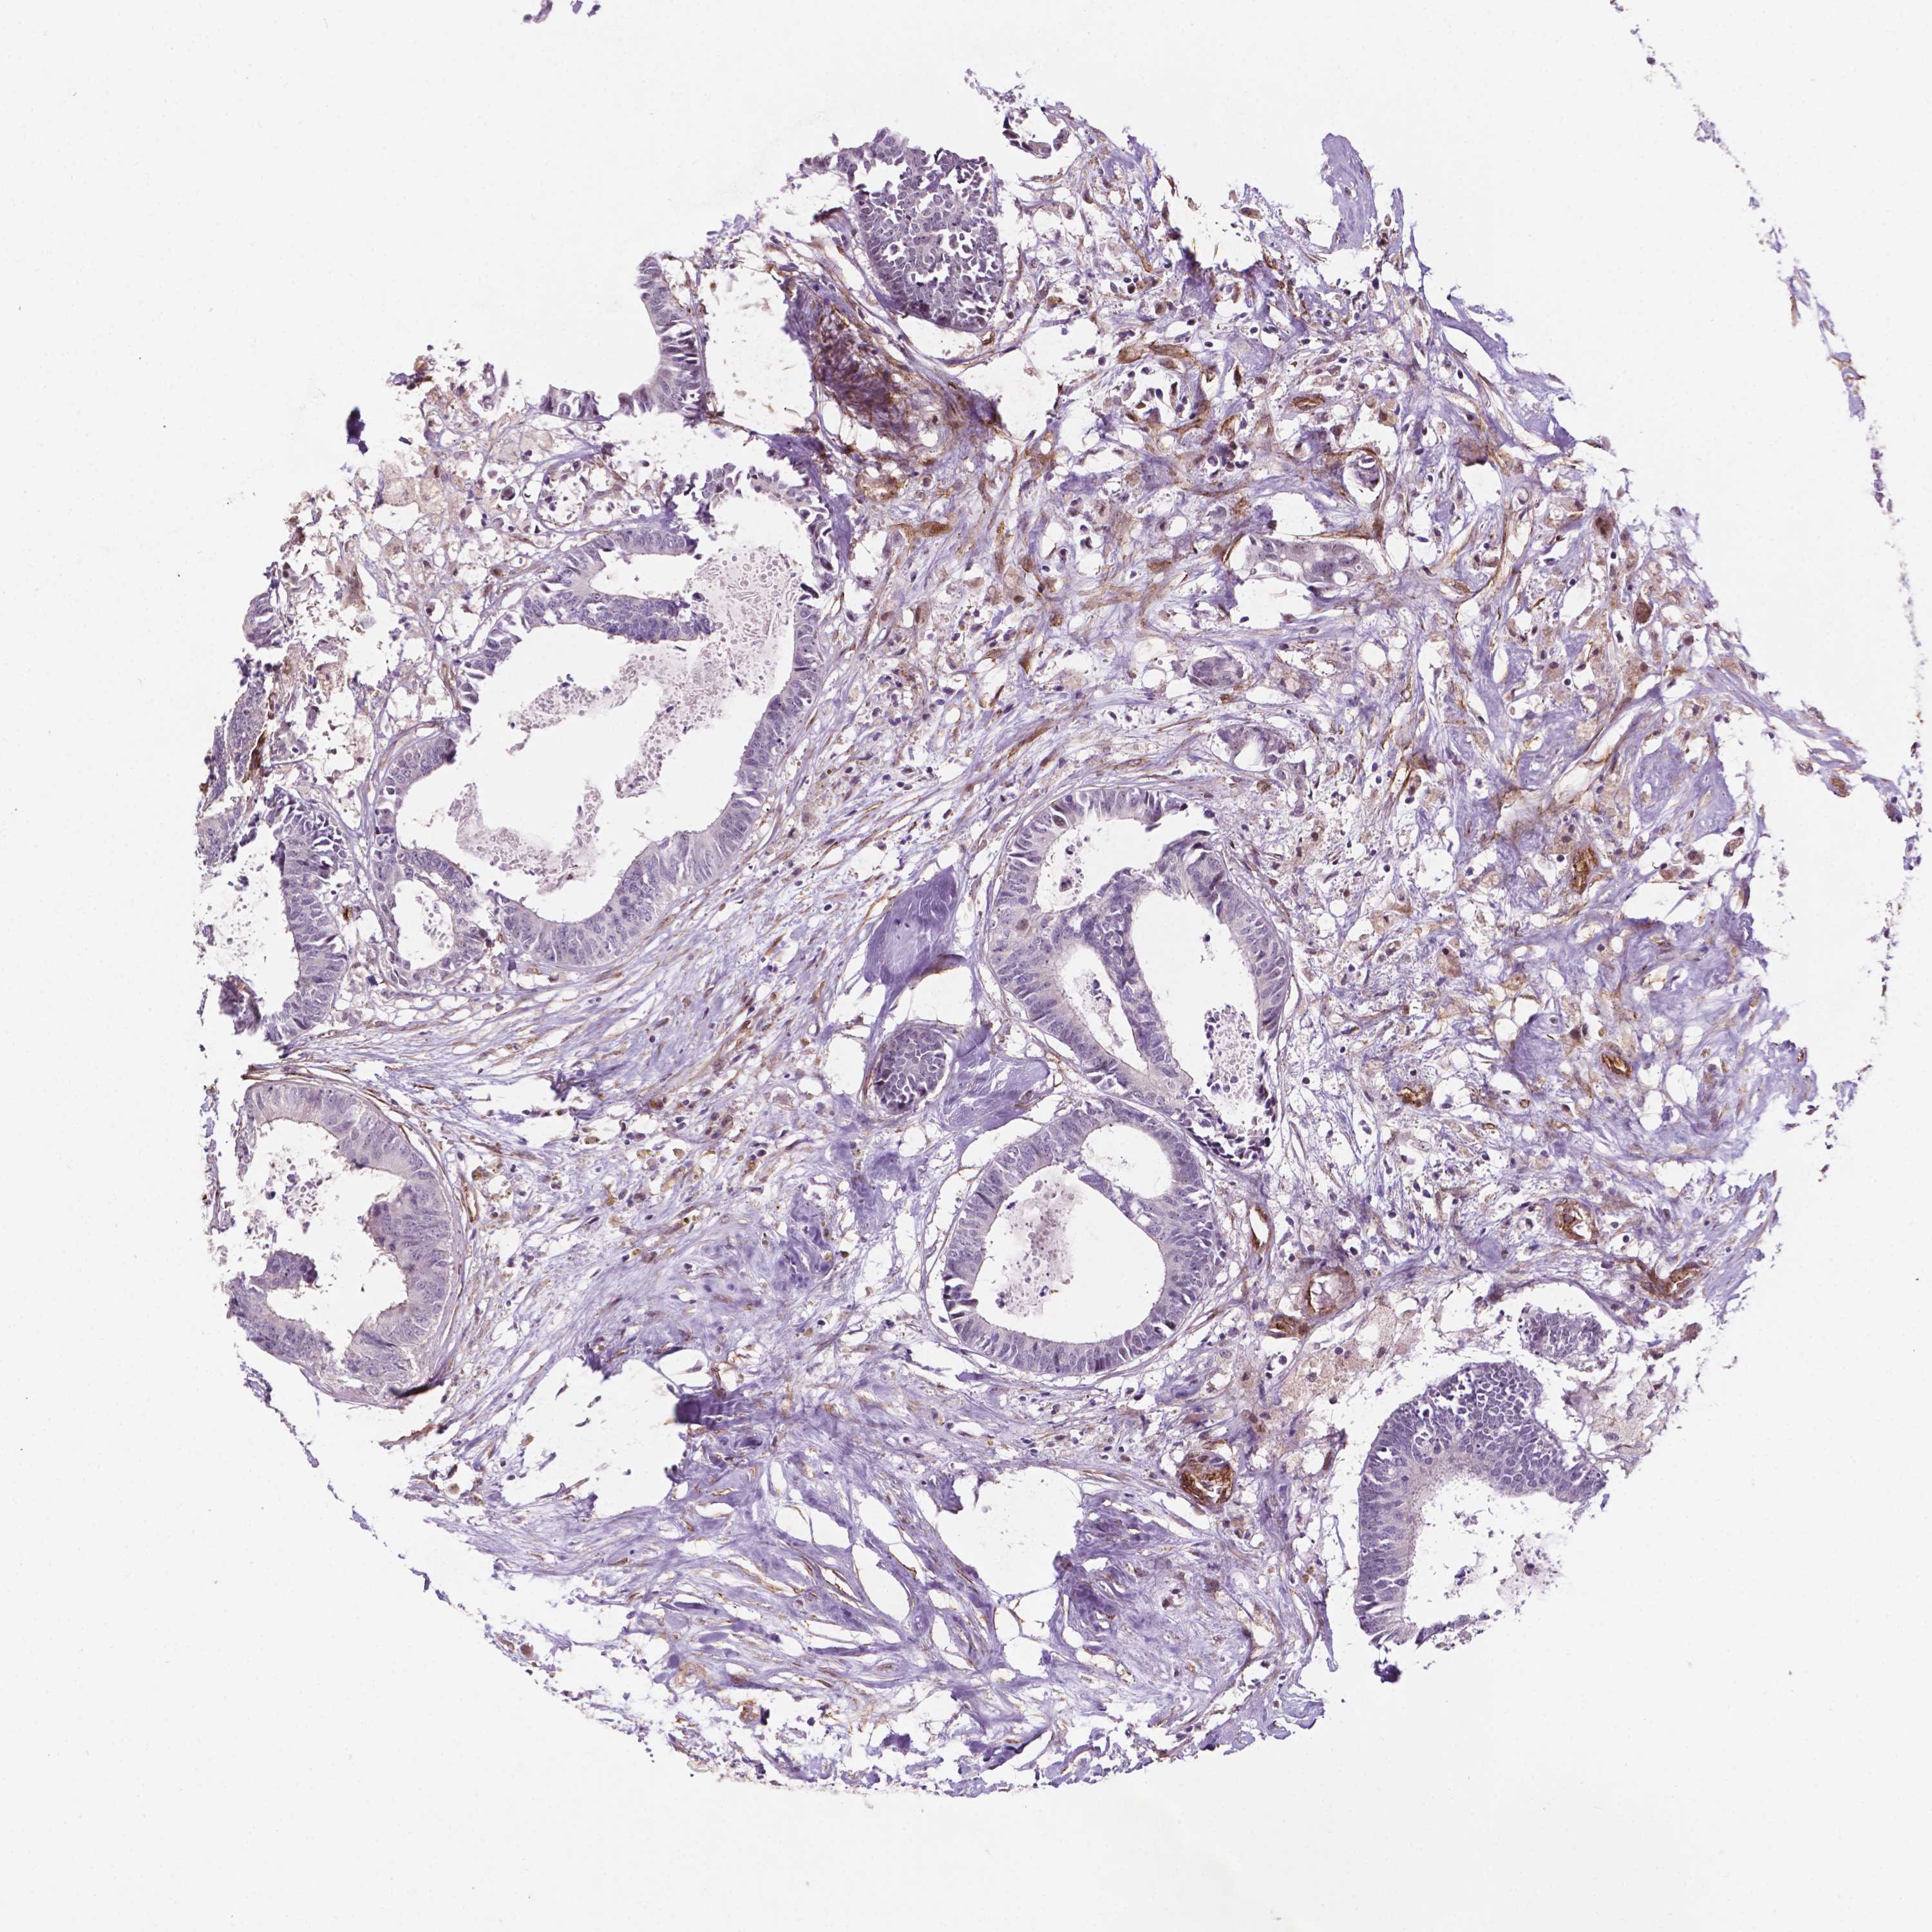

CANCER COLORECTAL CANCER Show tissue menu

Colorectal cancer

Human cancer